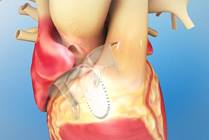

Hypoplastic Left Heart Syndrome

Hypoplastic left heart syndrome (HLHS) is a congenital heart defect where most of the structures on the left side of the heart are small and underdeveloped. The Hybrid approach, developed by surgeons at Nationwide Children's Hospital, is an alternative to Norwood open heart surgery for HLHS.